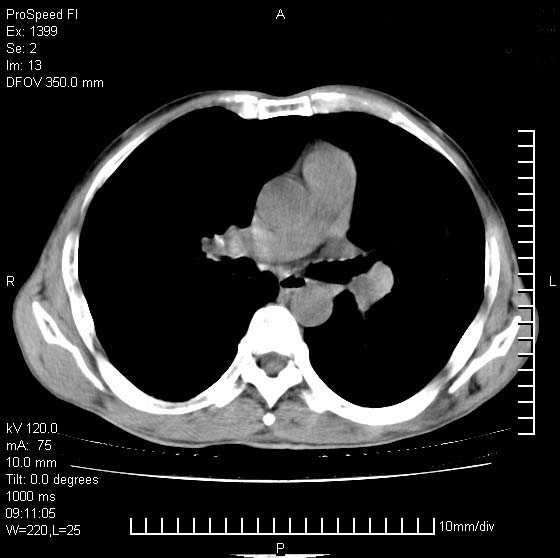

以下是引用rgsyyf在2007-1-19 11:05:00的发言:[br]左肺上叶见形态不规则巨大软组织肿块影,边缘呈分叶征,纵隔内隆突下见肿大淋巴结,右肺内另见一不规则结节影 .考虑:左肺周围性肺癌伴纵隔即右肺内转移.